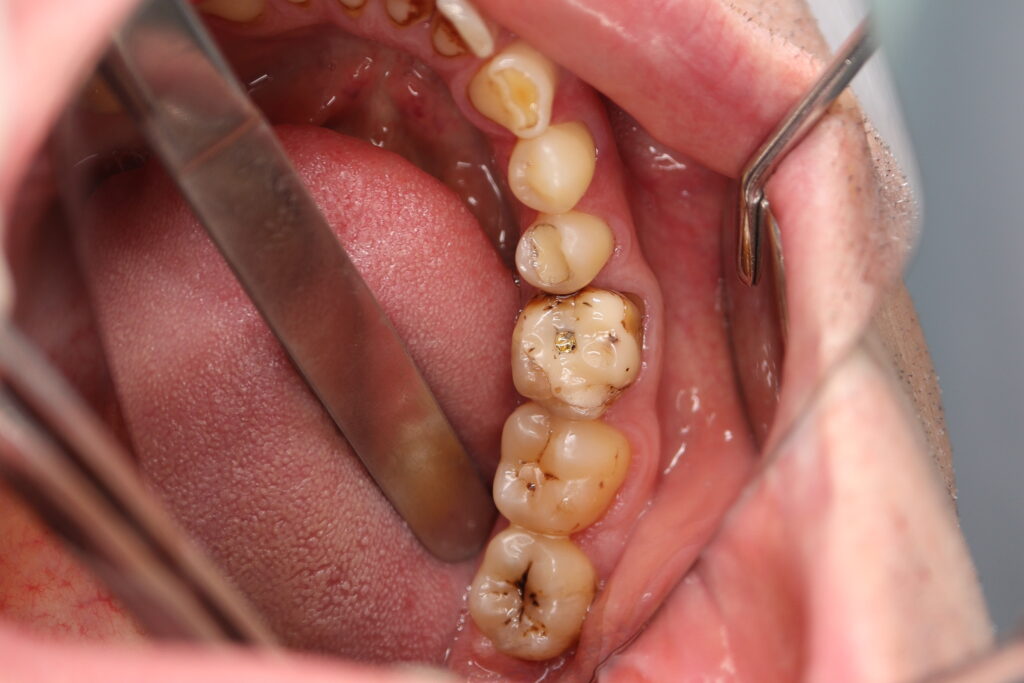

Ситуация до лечения

Пациент обратился с жалобами на эстетические недостатки.

Диагноз: Частичная адентия, клиновидные дефекты, гипоплазия эмали.

пациент до имплантации